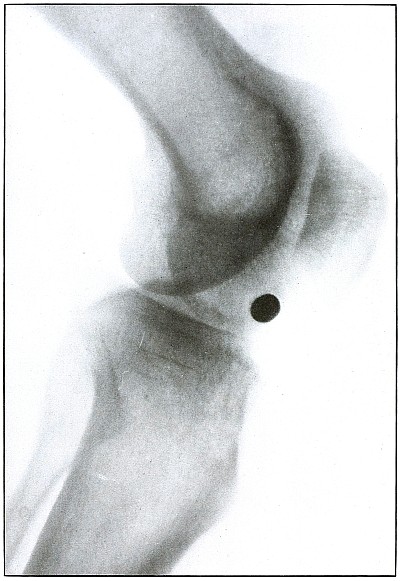

Plate 59.

_

[Pg 129]

Rifle—Plate 59.

LOWER EXTREMITY.

Gunshot Wound of the Left Knee-Joint,

with Lodgment of the Missile in the Joint.

The course of the bullet was transverse, entering the capsule posterior to the patella without injury to the bone.

As its shadow projection is almost circular, the bullet must be standing almost on its end pointing toward the plate with its long axis almost parallel to the line of projection.

As the fibular side of the leg lay next to the plate and as the only slightly enlarged shadow of the bullet indicates it to be near the plate, its position is in the joint near the fibular side.

As the bullet is undeformed and its penetrating power very slight, its velocity was that of extreme range.

The emergency treatment, is, of course, a simple antiseptic dressing with the leg held in the most comfortable position by muscular action.

The subsequent treatment is removal of the bullet when proper surgical conditions obtain. [Pg 130]